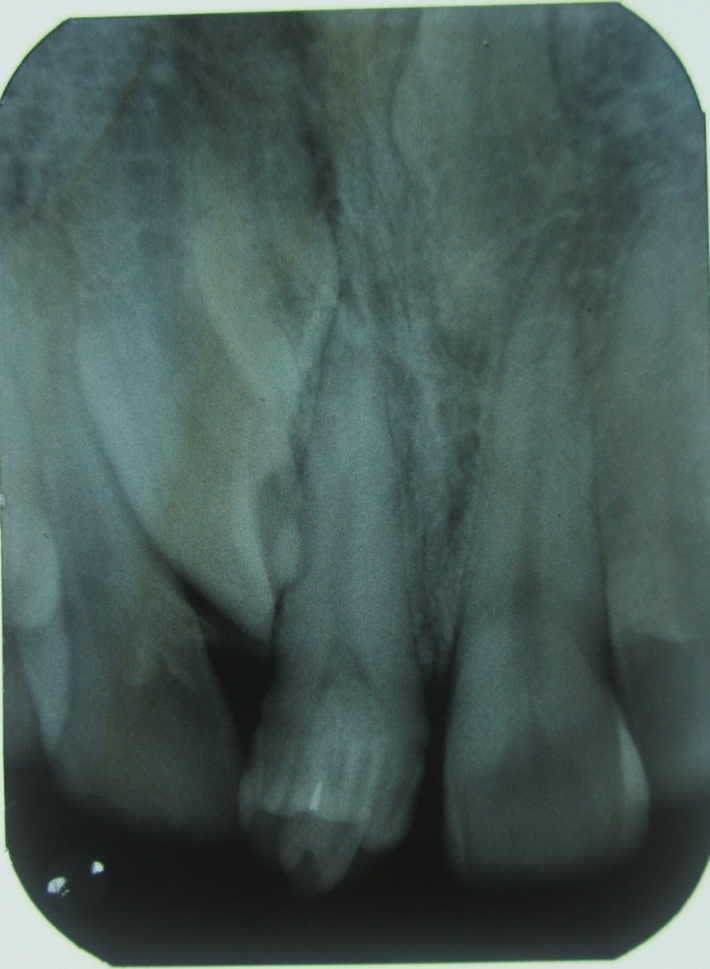

A 32-year-old male patient reported to the Department of Oral Medicine and Radiology for routine check-up. This was the patient’s first visit to a dentist. His medical and family histories were non-contributory. There were no findings indicative of any syndrome. An intraoral examination of maxillary right central incisor revealed a morphologically altered crown with multiple small cusps and a prominent central cusp (Figures 1 and 2). There were 5 small cusps and a prominent central cusp. Presence of talon cusp in relation to teeth #12, #13 and #33 was also seen. Mild stains were present on the occlusal surface of central incisor with pit caries. Intraoral periapical radiograph revealed prominent talon cusp at the center surrounded by small cusps along with three impacted supernumerary teeth at the periapex. The root, lamina dura and periodontal ligament space of tooth #11 appeared to be normal (Figure 3). Examination of the remaining dentition showed no obvious abnormalities. The patient was told about the condition. Routine scaling and oral prophylaxis were performed. Prosthetic crown in relation to tooth #11 was planned to correct the esthetic appearance and surgical removal of impacted teeth was suggested. Since the patient was asymptomatic, he refused to undergo extraction of the impacted teeth. However, he was advised to undergo prophylactic enameloplasty of the talon cusps, followed by topical application of a desensitizing agent. He was also informed about the possible consequences of the impacted teeth and a regular clinical and radiographic follow-up of the impacted tooth was suggested.

Figure 2.IOPA radiograph showing a central prominent cusp surrounded by small cusps and periapical area showing three impacted supernumerary teeth

.

Intraoral radiographs play a crucial role in the diagnosis of talon cusps and other associated pathologies. Radiographically, it may appear typically as a V-shaped radiopaque structure, as in true talon or semi-talon, or be tubercle-like, as in trace talon, originating from the cervical third of the root. This appearance varies with the shape and size of the cusp and the angle at which the radiograph is taken.15 In the present case, the tooth showed a central large projection surrounded by small cusps with no evidence of periapical changes.